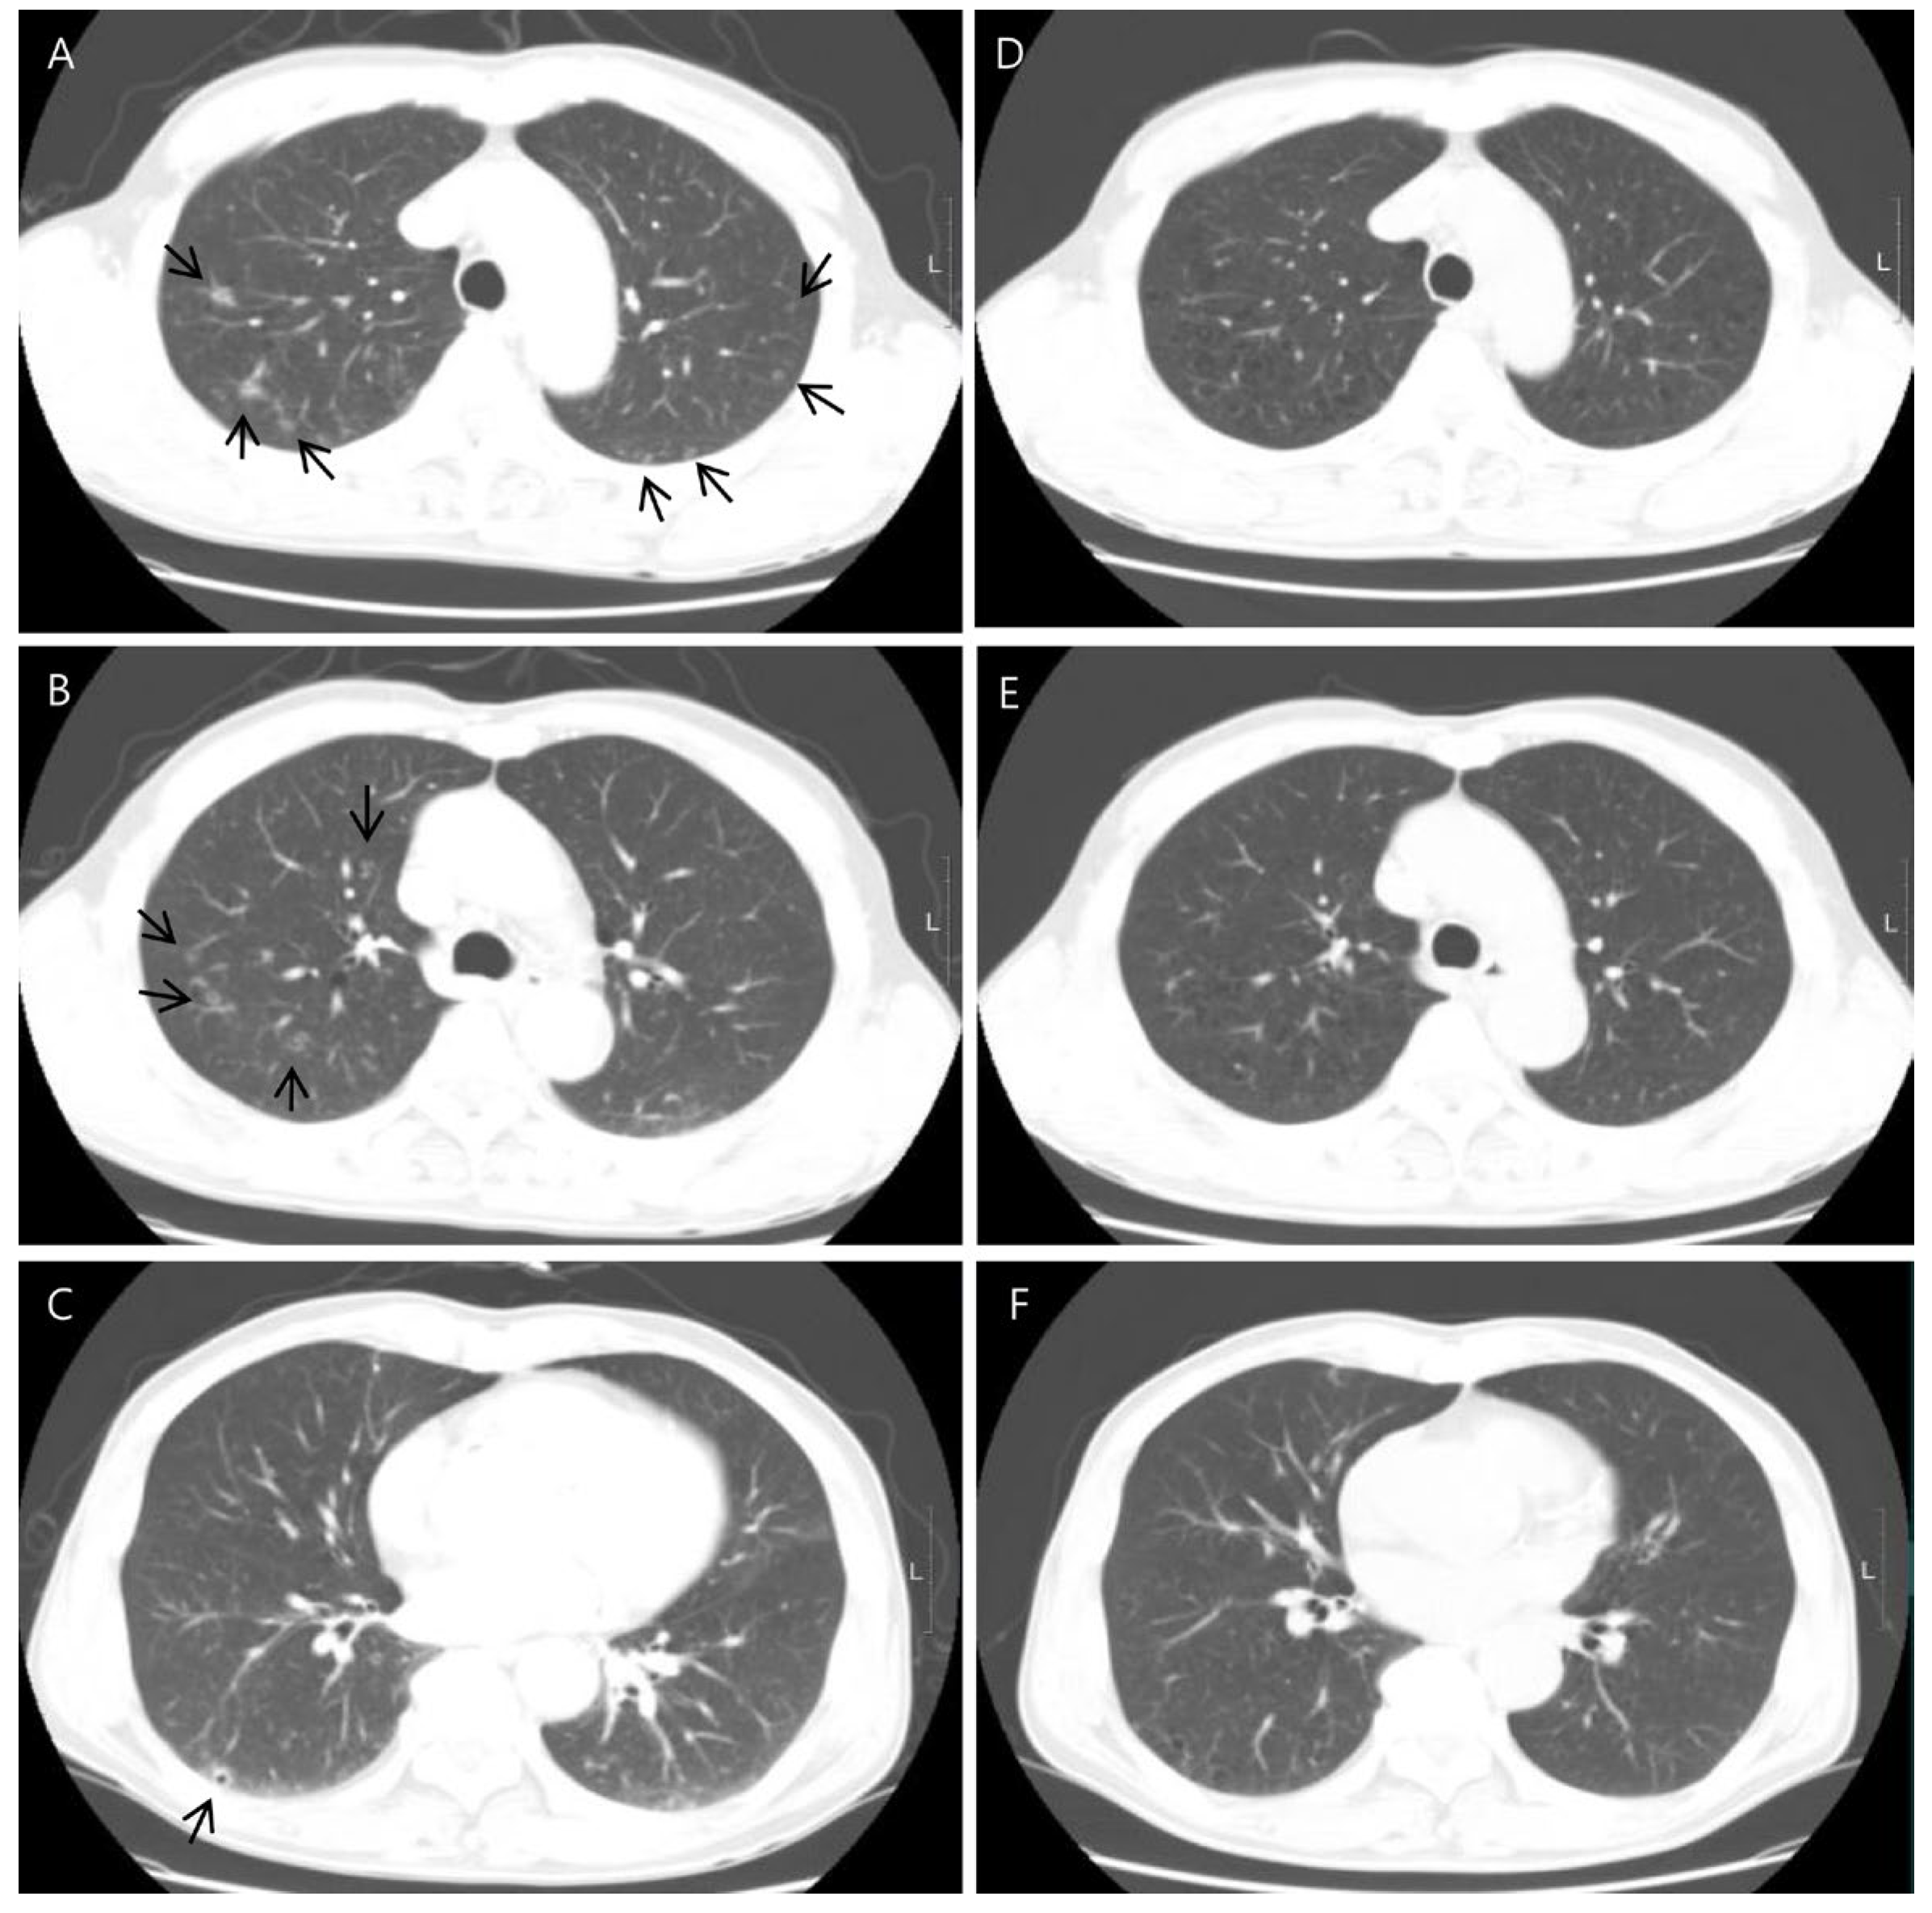

Chest contrast-enhanced CT revealed multiple peribronchial, centrilobular, and cavitary nodules in both lungs (Figure 2), and they have upper lung predominance. The radiologist considered this to be pulmonary metastasis from colorectal cancer first and an infectious condition second. Abdominal CT showed a 2 cm sized, ill-defined lesion in segment 5/6 of the liver (Figure 3). As a differential diagnosis for the solitary hepatic lesion, we considered sclerosing hemangioma, inflammatory pseudotumor, or metastasis. Laboratory results showed only a mild increase in the eosinophil ratio (6.6%). Except for that, no abnormalities were found in the coagulation system or general biochemical tests. Serologic markers for hepatitis B and C, acid-fast bacteria (AFB) stain, and AFP culture were negative. Regarding tumor markers, carcinoembryonic antigen and carbohydrate antigen 19-9 were normal. At that time, he did not take any medication or show signs of infection or other systemic symptoms such as fever or night sweats. In addition, his exact history of previously eating uncooked cow liver or meat is unclear.

Figure 2.

Axial chest CT showed multiple cavitary lung nodules in both lungs with upper lung zone predominance ((A–C), arrows). CT images obtained 5 months after showed the disappearance of the multiple cavitary nodules (D–F).

Liver magnetic resonance imaging (MRI) was performed to differentiate the pulmonary and hepatic lesions from another possible diagnosis. It revealed a 1.5 cm ill-defined nodular lesion contiguously extending into the liver capsule (Figure 4). These findings mostly likely represented liver fluke disease. The diagnosis of toxocariasis was confirmed through the presence of antibodies to Toxocara canis by enzyme-linked immunoassay (ELISA). Other parasite antibody tests, including Clonorchiasis sinesis, Paragonimus westermani, Taenia solium, Spirometra mansoni, Fasciola hepatica, Amoeba, Trichinella spiralis, and Schistosoma, all yielded negative results. Eventually, his colon cancer was treated with laparoscopic low anterior resection. After discharge, the patient took oral albendazole by himself. After 3 months, chest and abdominal CT was performed for the postoperative routine follow-up, and it showed a shrinkage of all pulmonary and hepatic lesions compared to the previous imaging. Finally, after 5 months, the entire multiple cavitary lung and the hepatic nodules disappeared (Figure 2 and Figure 3). In addition, the eosinophil ratio decreased from 6.6% to 0.4%.